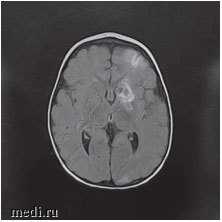

Рис. 3. МРТ головного мозга: ишемические изменения в бассейне левой средней мозговой артерии и атрофия коры головного мозга в височной и лобной долях слева

Консультация проф., зав. кафедрой неврологии детского возраста РМАНПО Зыкова В.П. от 14.03.17: ветряночный энцефалит с высокой вероятностью церебрального васкулита. По данным видео-ЭЭГ-мониторинга, выявлена эпилептиформная активность теменно-лобной лотенции. С учетом клинико-ЭЭГ-проявлений рекомендуется продолжить антиконвульсантную терапию в течение 6 месяцев от начала заболевания, с повторным видео-ЭЭГ-монторингом.

Консультация в НПЦ медицинской радиологии ДЗМ канд. мед. наук, доц. Петряйкина А.В. от 23.03.17: по результатам представленных КТ и МРТ изображений, учитывая клиническую картину вероятно речь идет о течении ветряночного VZV. Зона поражения затрагивает корково-подкорковые области левого полушария (всех долей), область головки хвостатого ядра. Вероятно, имел место васкулит с поражением периферических отделов сосудистого русла, без убедительных данных за геморрагический компонент.